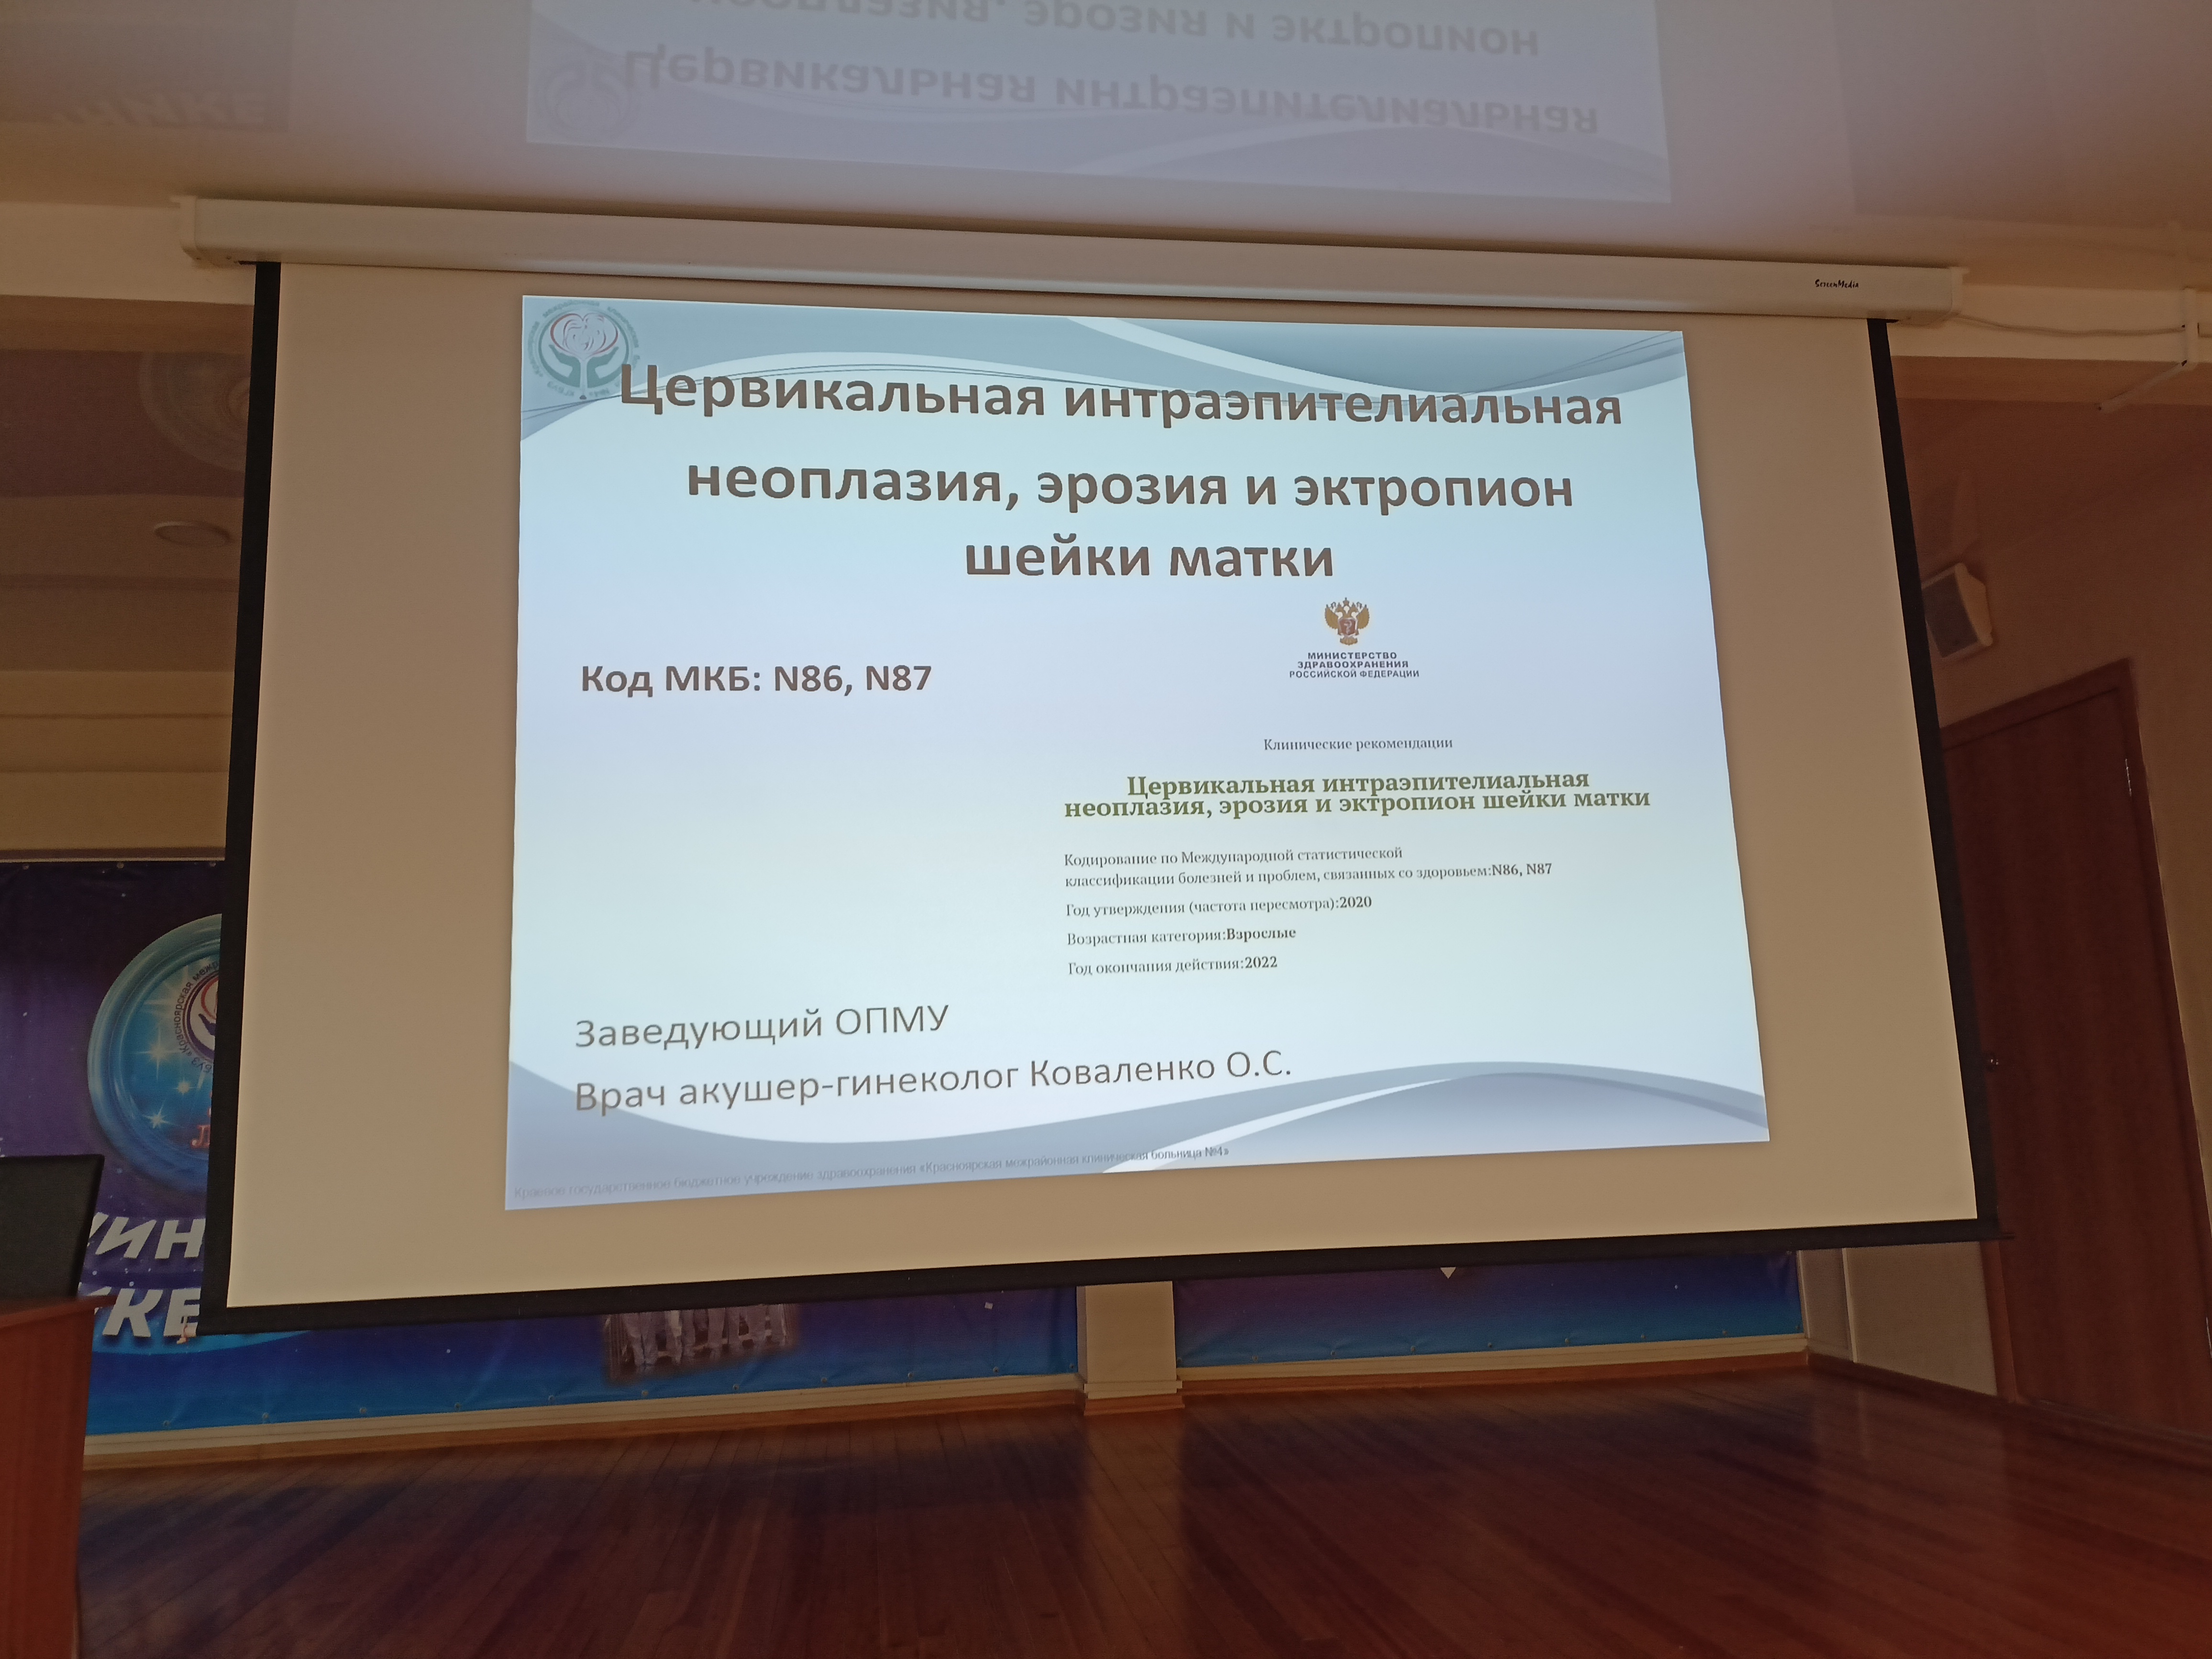

18.09.2025

Делегация с Кутузова приняла участие в конференции по качеству

Подробнее...

13.09.2023

Специалисты КГБУЗ "КМКБ № 4" примут участие во Всероссийской НПК "Практика разработки и внедрения СМК в медицинской организации"

Подробнее...